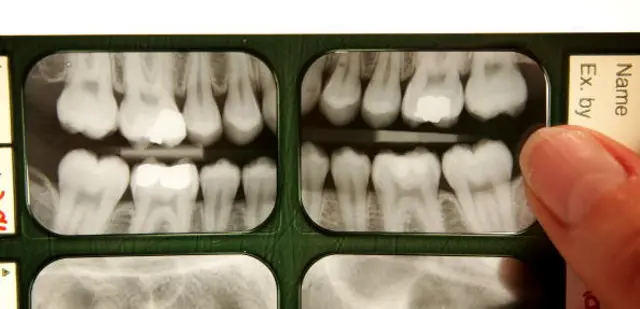

最近,另一些研究则关注牙齿自我修复的方法。加利福尼亚的牙医、美国口腔协会发言人鲁奇·萨赫塔(Ruchi Sahota)建议将牙齿的解剖结构想象为一只苹果。“牙齿有一层薄薄的牙釉质外壳,就像苹果皮一样,它保护着牙齿的内核,也就是牙本质。牙齿也有神经,就像苹果的籽一样。”她说,“龋齿在牙釉质中形成,当它进入牙本质时,你就需要找牙医补牙了。当它进入神经中,你就需要做根管治疗了。”